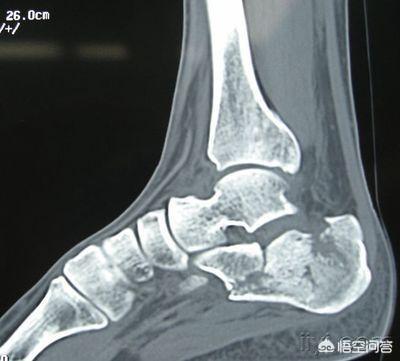

1、可能是畸形愈合:跟骨有6个面,4个关节面,一旦畸形愈合出现关节面不平整。

那么,最后走路时由于关节的不平整而出现疼痛,此时,你就不能脱拐!

这就是为什么畸形明显的跟骨骨折需要手术的原因,特别是粉碎性骨折!

题主未曾提到跟骨骨折是否做了手术,如果未做手术,骨折端错位明显则会畸形愈合,或者有些手术复位不良,都会导致骨折畸形愈合,关节面不平整,造成骨质增生,引发疼痛,而不敢下地负重行走。